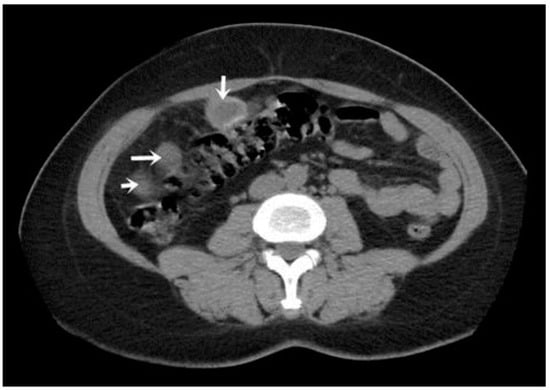

Figure 4. Peritoneal and segment V cyst (indicated by arrows).

A CT examination revealed multiple cystic images in the hepatic segments V, VI, and VII, with subhepatic extension and involvement at the fissures of the venous ligament. Cystic images were also observed in the anterior abdominal wall and submesocolic (Figure 5, Figure 6, Figure 7, Figure 8 and Figure 9). Blood tests showed no significant abnormalities, and ELISA determination of IgG class antibodies to Echinococcus granulosus was positive at 1.66 IV (with values considered negative at ≤0.9 IV and positive at ≥1.1 IV).

The imaging highlights hepatic cysts in segments V, VI, and VII, a large cystic formation in the round ligament, a cyst in the parietal peritoneum, two cysts in the greater omentum, and two cysts located in the submesocolic enteral mesentery.